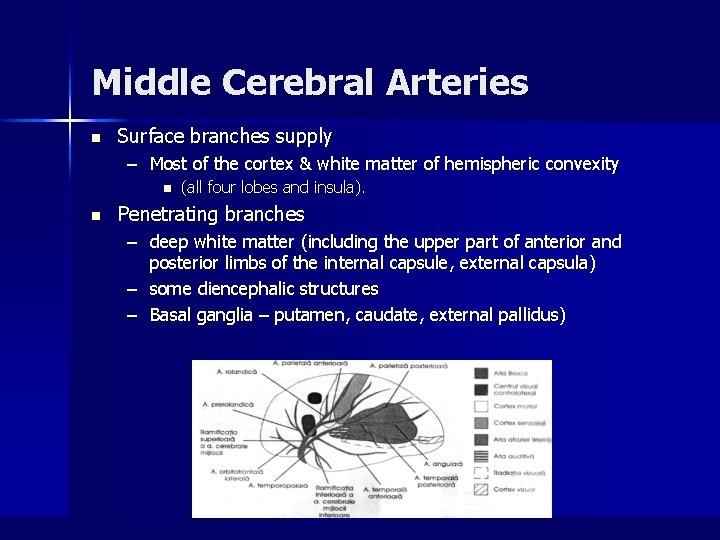

Middle Cerebral Arteries n Surface branches supply – Most of the cortex & white matter of hemispheric convexity n n (all four lobes and insula). Penetrating branches – deep white matter (including the upper part of anterior and posterior limbs of the internal capsule, external capsula) – some diencephalic structures – Basal ganglia – putamen, caudate, external pallidus)